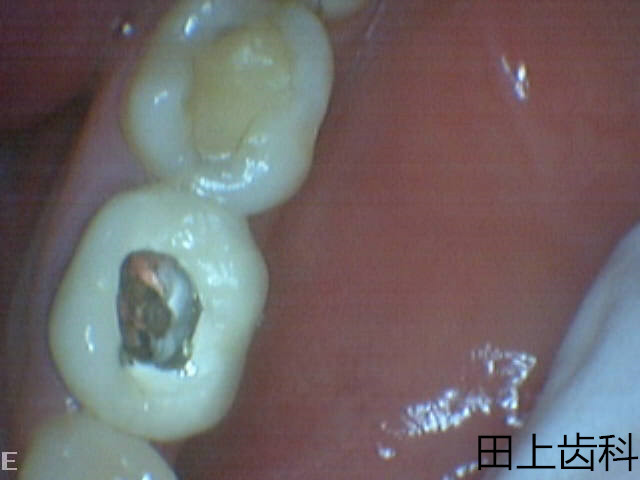

根管治疗